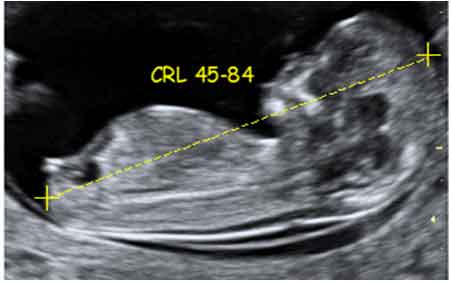

It is clear that although the gold standard of screening is the combined test using FMF software and accredited labs, this may be a bit difficult to implement at a government hospital level. Dr Punia was pleasantly surprised to learn that a number of fetal abnormalities can be picked up at the First trimester scan and requested the FMFI team to give hima document of the “always detectable 9” structural abnormalities that should not be missed on the scan.This along with a correctly taken CRL and NT should constitute the absolute minimum requirements of scanning at the peripheral level.

Minimum requirements of the First trimester scan at the Peripheral level